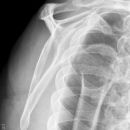

Dislozierte subcapitale Fraktur mit Tbc majus